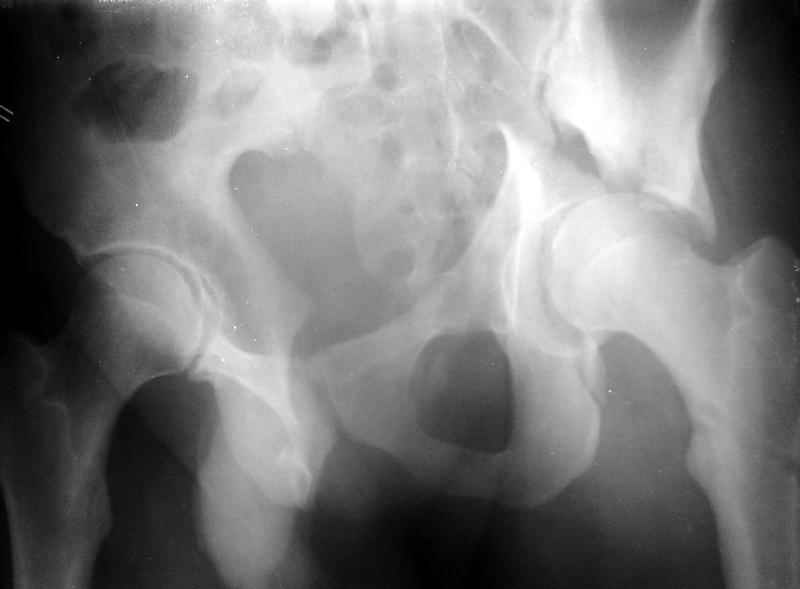

Для уточнения диагноза необходим обзорный снимок таза и Judet проекции. Судя по присланной короткой рентгенограмме, один из компонентов перелома - отрыв свода, точно имеется ступенеобразная деформация нагружаемой поверхности и без открытой репозиции ничего хорошего не будет. Если в ближайшую неделю восстановительная опеперация не будет сделана, то лучше потом и не пытаться, а ждать сращения бедра для эндопротеза.

Сегодня на приеме был пациент, чьи начальный снимок напомнил обсуждаемый сейчас (см. выше). Снимки в других проекциях, показывающие истинный характер повреждения, ниже. Это inlet проекция (вход в таз) и запирательная проекция Judet.